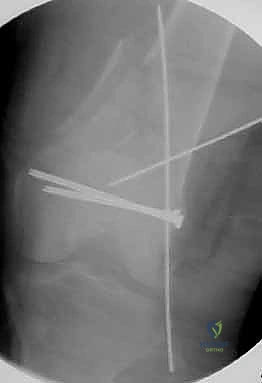

المرحلة الرابعة: التثبيت النهائي بالشرائح والمسامير (Fixation)

يتم استخدام "شرائح الإغلاق التشريحية" (Anatomical Locking Plates) المصنوعة من التيتانيوم عالي الجودة. هذه الشرائح مصممة خصيصاً لتأخذ شكل الجزء السفلي من عظم الفخذ. يتم تمرير الشريحة أسفل العضلات وتثبيتها بمسامير تغلق داخل الشريحة نفسها (Locking Screws)، مما يوفر ثباتاً ميكانيكياً هائلاً، حتى في حالات العظام الهشة.

في بعض الحالات المعقدة جداً، قد يتطلب الأمر استخدام شريحتين (Dual Plating) لضمان عدم تحرك الكسر أثناء فترة التعافي.